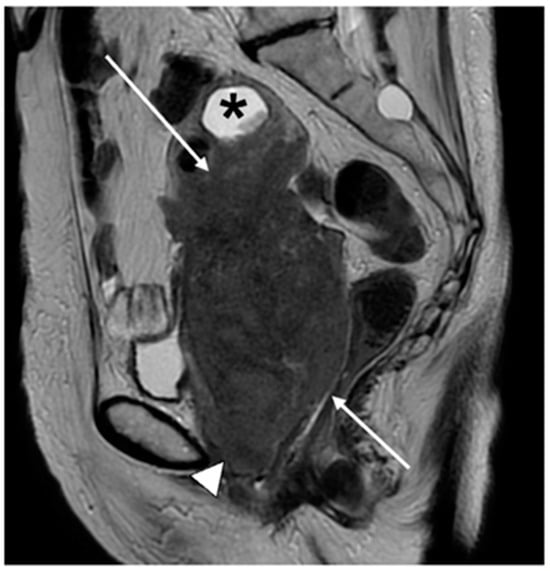

6. FIGO Stage III

7. FIGO Stage IV